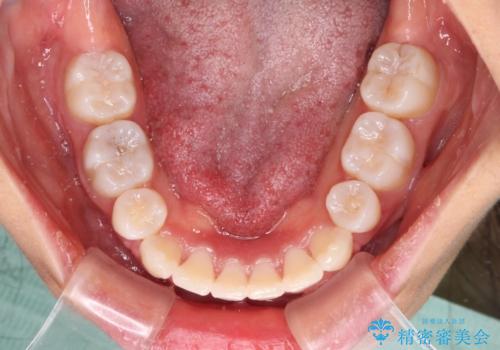

治療前の上下正中はずれていましたが、骨格的な上下左右差はあまり認められなかったため、正中を揃えて治療を終えることができました。

1年半ほどで治療を終えることができるとは我々も想像しておらず、患者様には大変満足していただきました。